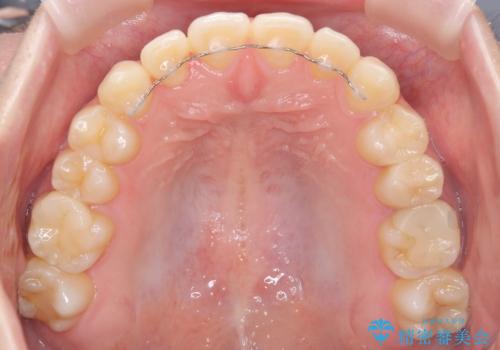

インビザラインを希望されておりましたが、20時間もつけることができなかったためワイヤー矯正にて叢生の改善を行っています。

右上の側切歯(前から2番目の歯)が90度程度ねじれている状態でしたが、1月に1回のワイヤー交換できれいに並ぶことができ満足いただけました。

捻れた歯の治療に関しては、ワイヤー矯正の方が仕上がりがきれいに治りやすいです。